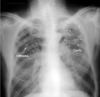

What is shown in the image?

Cavitating Squamous Cell Cancer